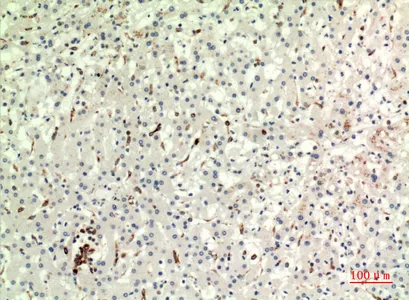

CMTM6 Rabbit Polyclonal Antibody

Cat: APRab09089